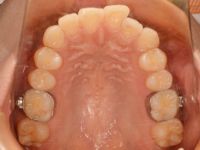

最初に、奥歯に金属製の輪っか(バンドといいます)をつけます。バンドにはいろいろな大きさのものがあり、歯の大きさにピッタリ合うものを探し、いくつか合わせていきます。ピッタリ合っていないと治療中に装置が外れやすくなってしまい、治療がうまく進まない原因になってしまいます![]()

そして、取った歯型にバンドを戻し、石膏を流します。石膏が固まると、下のように口の中と同じ状態の模型が出来上がります![]()

この模型上で装置を作ります。装置を作ってくれるのは、歯科技工士の西村綾子さんです![]()